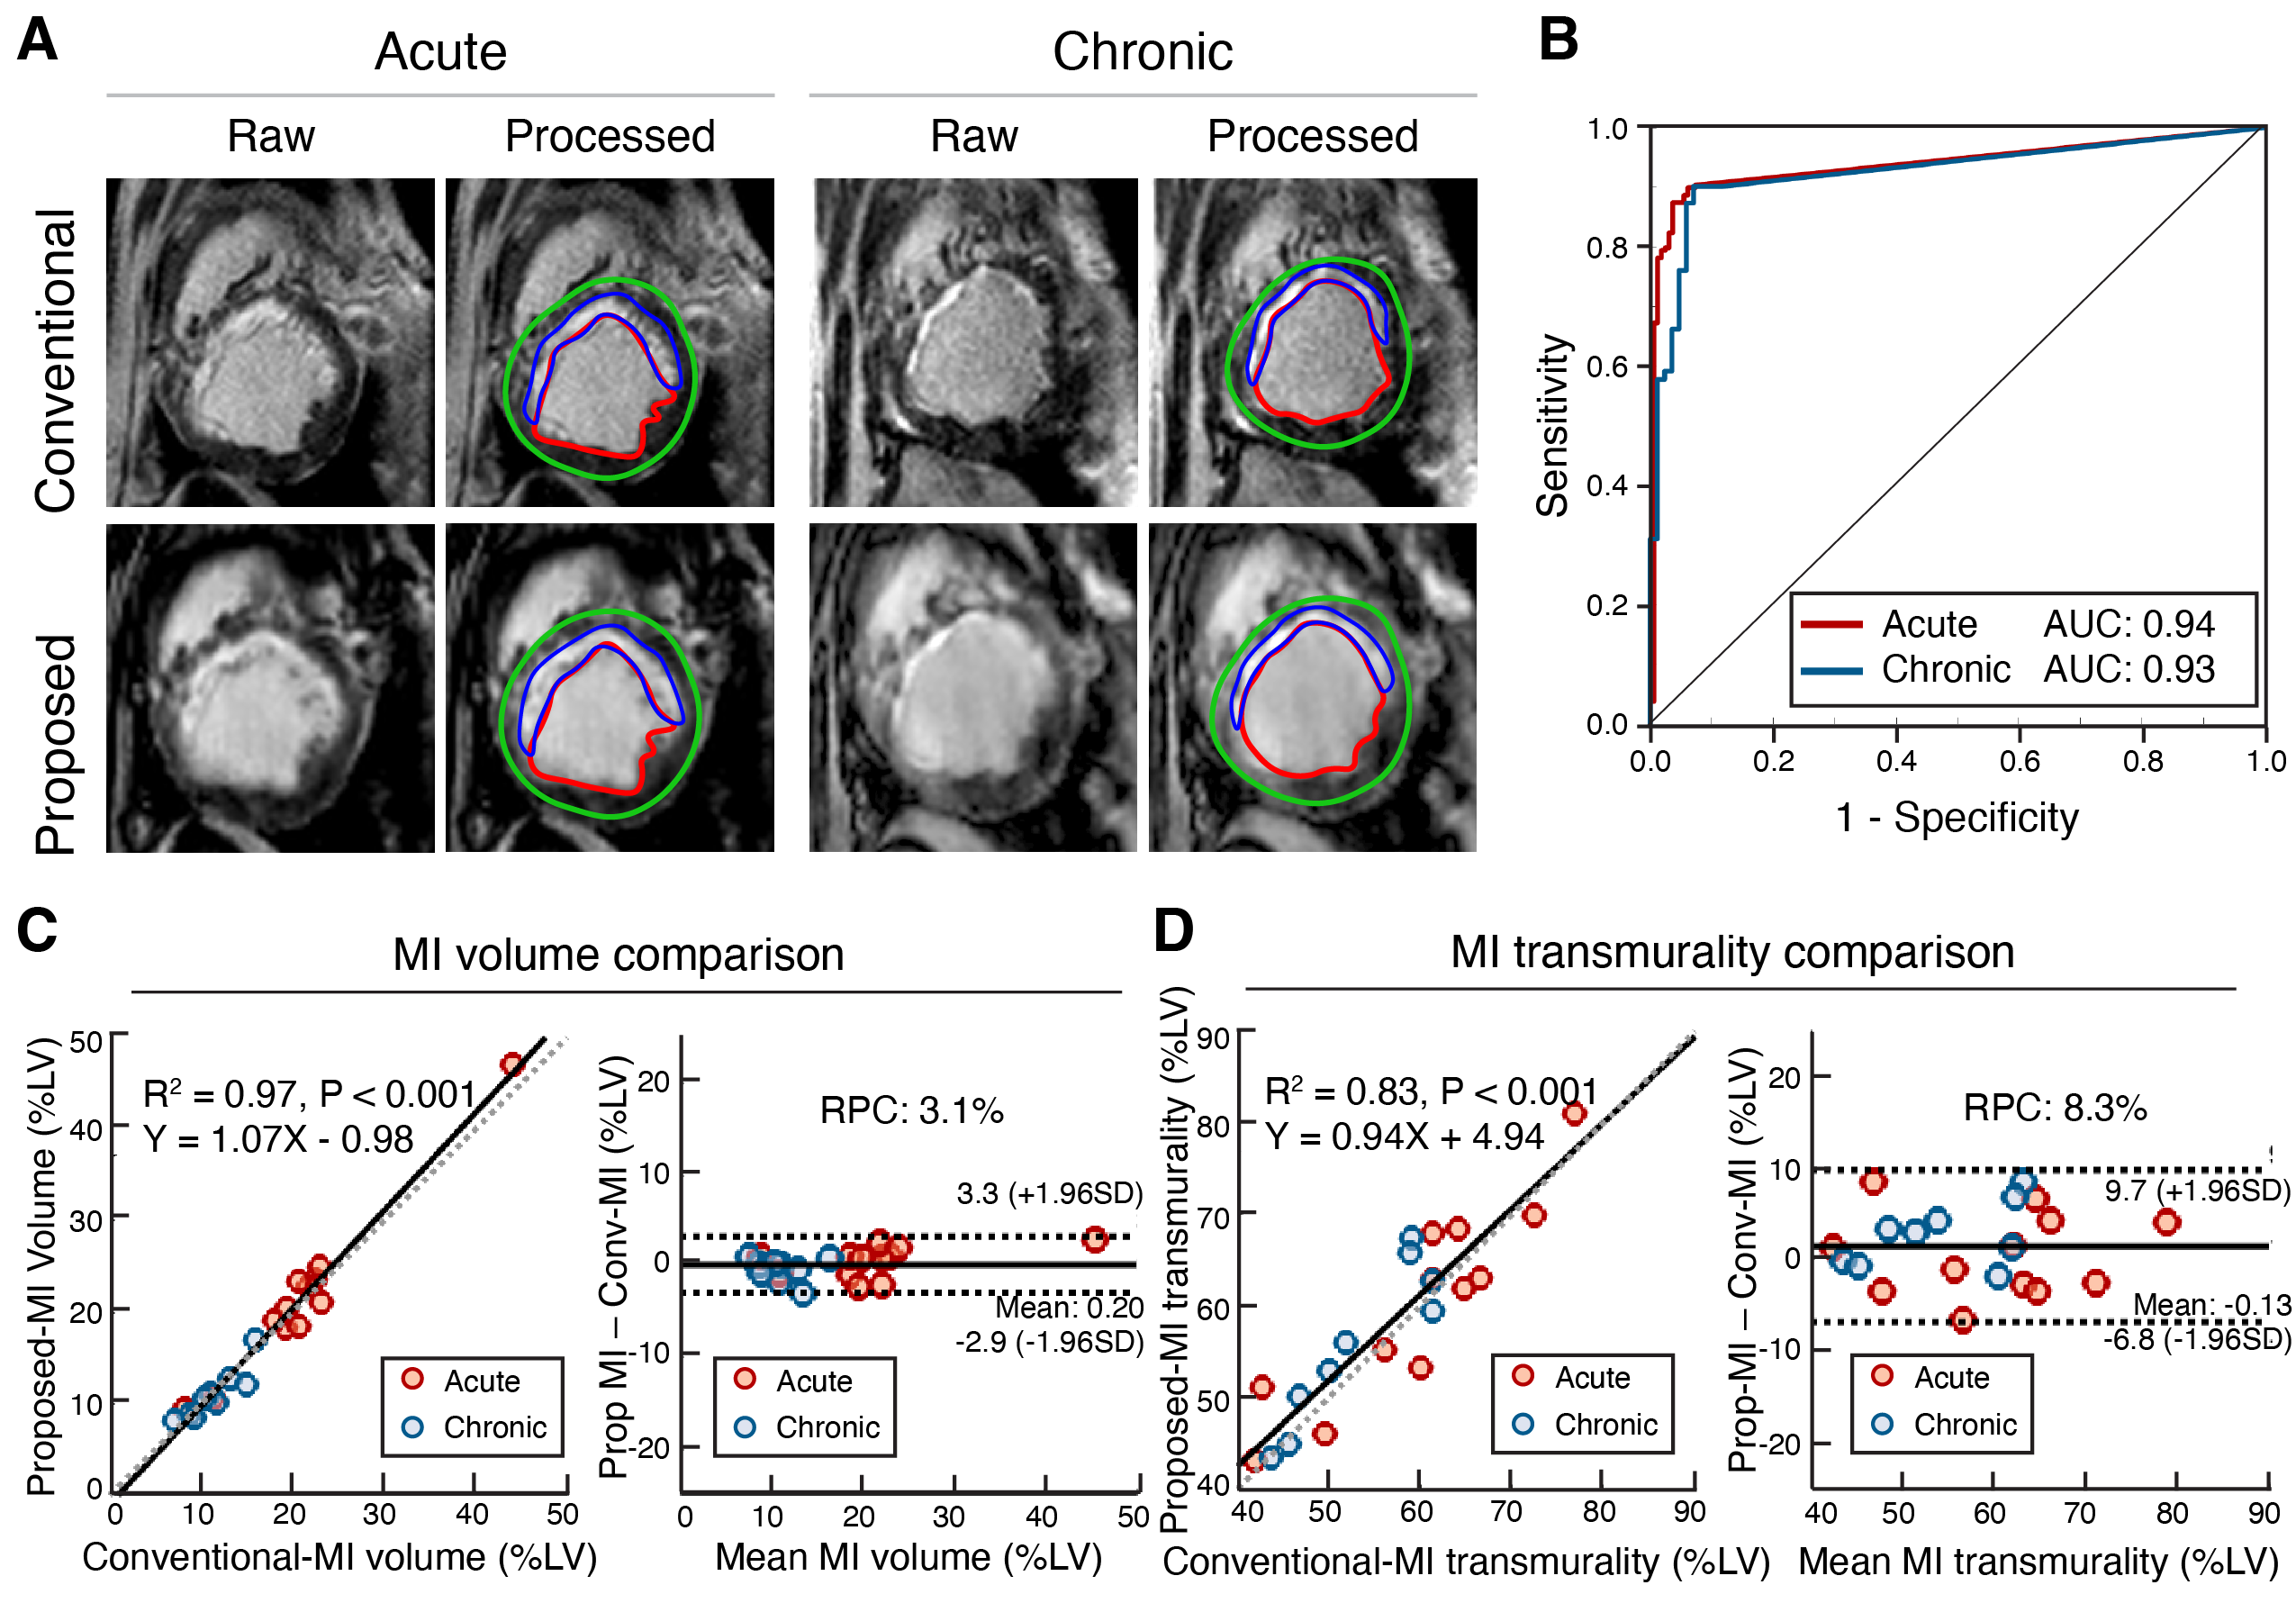

Results: The proposed method reduced acquisition time by >50%. There was no difference in LVEF: 31.28±5.42% vs. 34.34±3.89%, P = 0.54. MI volume were comparable (%LV): MI volume - 16.30±8.93 vs. 16.17±8.23, P=0.57; and MI transmurality - 58.41±10.07 vs. 56.97±9.76, P=0.13. Detection of acute MI achieved AUC=0.94 and chronic MI AUC=0.93 (Fig. 2). MVO (%LV) and IMH volume (%LV) were also not different: MVO - 6.94±5.42 vs. 6.11±4.93, P = 0.17; IMH - 4.57±3.30 vs. 4.57±3.31, P = 0.98. Early and persistent MVO yielded AUC=0.93 and AUC=0.92, respectively (Fig. 3A-C). IMH volume showed equivalent quantification (4.6±3.3% vs. 4.6±3.3%, P=0.98; R²=0.95), with reduced off-resonance artifacts. AUC for IMH detection were 0.93 in the acute phase and AUC=0.92 in the chronic phase (Fig. 3D-F). Histopathology confirmed cardiac MRI evidence of tissue injury (Fig. 3G).

Figure 2. MI Size and Transmurality with Proposed and Conventional Approaches. A) Representative images from canine acquired using conventional and the proposed approaches. D) ROC analysis for MI detection for subjects with acute and chronic timepoints, along with corresponding AUC, are shown. C) – D) Linear regression analysis and bland-altman analysis of MI size and MI transmurality determined using the Conventional and the proposed approaches, across all animals (along with line and equation of best fit, R2 and P values) and corresponding Bland-Altman analysis (along with RPC) are shown.

Figure 2. MI Size and Transmurality with Proposed and Conventional Approaches. A) Representative images from canine acquired using conventional and the proposed approaches. D) ROC analysis for MI detection for subjects with acute and chronic timepoints, along with corresponding AUC, are shown. C) – D) Linear regression analysis and bland-altman analysis of MI size and MI transmurality determined using the Conventional and the proposed approaches, across all animals (along with line and equation of best fit, R2 and P values) and corresponding Bland-Altman analysis (along with RPC) are shown.  Figure 3. Validation between conventional 2D (Conv.) and proposed (Prop.) measures of microvascular obstruction (MVO) and intramyocardial hemorrhage (IMH): A) and D) are representative subjects of MVO characterization and IMH characterization between the two methods, respectively. B) and E) are linear regression between the two methods in MVO and IMH characterization. C) and F) ROC analysis between the two approaches, the area-under-the-curve (AUC) of ROC analysis is shown. G) Histological validation of MI and IMH using Trichrome and Prussian Blue staining.